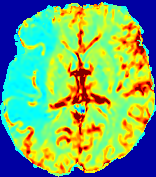

Slice #1Slice #2Slice #3Slice #4Slice #5Slice #6𝐕gt𝟐subscriptnormsuperscript𝐕gt2\|\bf{V}^{\text{gt}}\|_{2}Refer to captionRefer to captionRefer to captionRefer to captionRefer to captionRefer to caption𝐕est𝟐subscriptnormsuperscript𝐕est2\|\bf{V}^{\text{est}}\|_{2}Refer to captionRefer to captionRefer to captionRefer to captionRefer to captionRefer to captionRefer to caption1.51.51.51.21.21.20.90.90.90.60.60.60.30.30.30.00.00.0(mm/s)𝑚𝑚𝑠(mm/s)Destsuperscript𝐷estD^{\text{est}}Refer to captionRefer to captionRefer to captionRefer to captionRefer to captionRefer to captionRefer to caption0.0150.0150.0150.0120.0120.0120.0090.0090.0090.0060.0060.0060.0030.0030.0030.0000.0000.000(mm2/s)𝑚superscript𝑚2𝑠(mm^{2}/s)

Figure 14: PIANO identifiability testing: advection imaging via advection-diffusion. Top row shows 𝐕gt2subscriptnormsuperscript𝐕gt2\|{\bf{V}}^{\text{gt}}\|_{2} used for simulating ground truth pure advection. Rows below show the estimated 𝐕est2subscriptnormsuperscript𝐕est2\|{\bf{V}}^{\text{est}}\|_{2} and Destsuperscript𝐷estD^{\text{est}} on corresponding slices. Note that the plotted value scale for Destsuperscript𝐷estD^{\text{est}} is 0.01 of that for 𝐕gt2subscriptnormsuperscript𝐕gt2\|{\bf{V}}^{\text{gt}}\|_{2} and 𝐕est2subscriptnormsuperscript𝐕est2\|{\bf{V}}^{\text{est}}\|_{2}.

We use the same ‘Advection Imaging’ simulation of Sec. 4.2.1 as the concentration dataset for PIANO. However, instead of modeling pure advection (Eq. 15), we let PIANO estimate both velocity 𝐕estsuperscript𝐕est{\bf{V}}^{\text{est}} and diffusivity Destsuperscript𝐷estD^{\text{est}} via the advection-diffusion PDE (Eq. 2) underlying the proposed PIANO model. Fig. 14 shows the estimated 𝐕est2,subscriptnormsuperscript𝐕est2\|{\bf{V}}^{\text{est}}\|_{2}, and Destsuperscript𝐷estD^{\text{est}} fields for one patient. Although PIANO has the freedom to estimate both a velocity and a diffusivity field from pure advection, PIANO differentiates well between advection and diffusion: the estimated 𝐕est2subscriptnormsuperscript𝐕est2\|{\bf{V}}^{\text{est}}\|_{2} successfully reproduces the ground truth 𝐕gt2subscriptnormsuperscript𝐕gt2\|{\bf{V}}^{\text{gt}}\|_{2} governing the simulated advection process, just as it already did in the ‘Advection Imaging via Advection’ test (Fig. 12). More importantly, the estimated diffusivity Destsuperscript𝐷estD^{\text{est}} is orders of magnitudes smaller than 𝐕est2subscriptnormsuperscript𝐕est2\|{\bf{V}}^{\text{est}}\|_{2}, indicating the estimated diffusion is negligible compared to the estimated advection, which is highly consistent with the underlying pure advection of the simulated data.